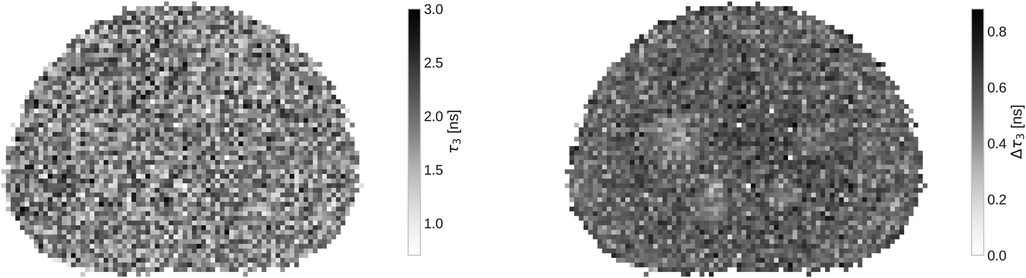

In Figure 3 a slice of the full oPs lifetime image, together with the fit error on τ3 with a 4×4×4mm3 binning, is presented. While the oPs lifetime image is not particularly interesting - after all, the phantom is filled with water - the marginalized uncertainty on τ3 clearly increases in the central region of the phantom. Note that only for the four largest spheres, the error decreases visibly.

Two grayscale images showing pixelated circular patterns with different shades of gray. The left image has a scale from one to three nanoseconds, labeled τ₃, while the right image ranges from zero to 0.8 nanoseconds, labeled Δτ₃.

Figure 3. Slice of the oPs lifetime image (left) and τ3 error (right) with 4×4×4mm3 voxels.

τ3’s uncertainty is seen in Figure 3 as well. The variation on τ3 across the whole phantom is quite large, given that the expected oPs lifetime should be the same across the whole phantom. In the right panel of Figure 3, only very few voxels have an error below 0.3ns. The mean uncertainty on τ3 across the slice shown in Figure 3 is 0.53ns. Only the four largest spheres of the phantom have a visibly smaller uncertainty compared to the phantom background.